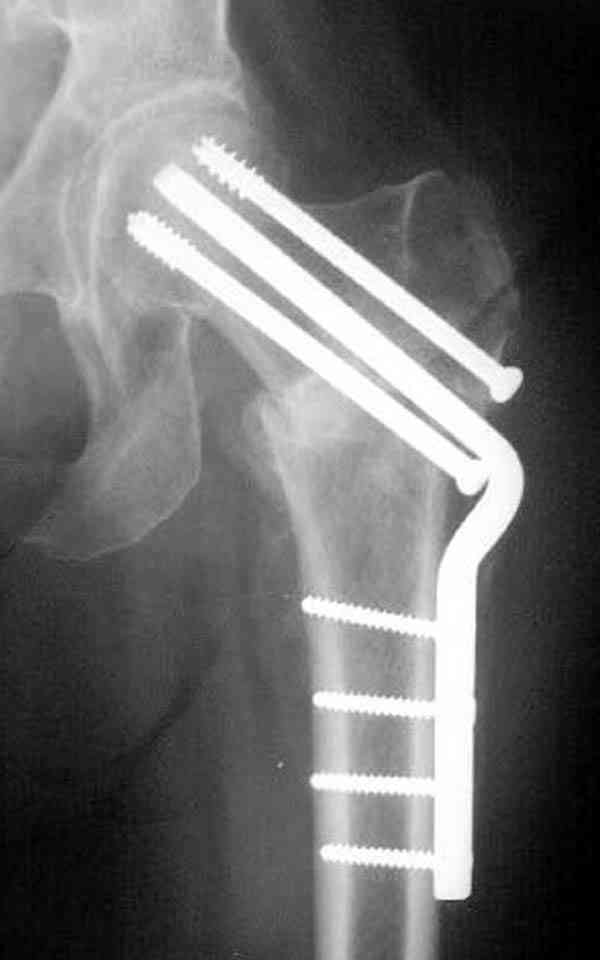

Спасибо, Антон. Я автор того сообщения по профилактическому армированию шейки бедренной кости, которое прозвучало на конференции, посвященной 50-летию создания АО. Мне тоже хотелось услышать вопросы по теме. Мы травматологи-ортопеды в первую очередь хирурги, а не терапевты. Почему в вопросе профилактики и лечения остеопороза мы ограничиваемся только консервативными методами лечения? Как можно практически научить больного не получать травмы, когда немало случаев возникновения переломов даже в постели. Первоначально идея армирования ШБК многих, при ком я озвучивал ее, шокировала, затем возникала дискуссия и большинство поддерживали эту идею. Мне бы очень хотелось развернуть дискуссию на странице этого сайта.

Кликните для загрузки файла P3230006.JPG

54KB (56062 bytes)

Отправитель: Анатолий Матвеев 22 Январь 2009, 18:11

Уважаемый Антон! У меня было всего три клинических наблюдения, снимки были продемонстрированы на московской конференции. Количества этих снимков хватило для подачи заявки, а затем и получения патента на изобретение. В свое время РОСПАТЕНТ потребовал подтверждения методики клиническими наблюдениями. У одной из больных действительно произошла повторная травма, и произошел подвертельный перелом на стороне армированной шейки бедренной кости (см. снимки). Это подтвердило основную идею изобретения - была сохранена и головка, и армированная шейка бедренной кости. Но тут не обошлось безпроблем. Анестезиологи отказались давать наркоз, а провести остеосинтез под м/а пластиной и винтом DHS не согласилась больная. Дальнейшее лечение скелетным вытяжением. На контр. Рентгенограмме через 2 месяца признаки формирования костной мозоли. Повторных обращений двух других пациентов не было. Для более детальных исследований и выводов необходимо значительно большее количество клинических наблюдений. Такие исследования могли быть проведены в условиях клиник медуниверситета. Напомню, я работаю в травмотделении провинциальной городской больницы. Насчет экспертов страховых компаний, так пусть они выскажут свое мнение. Армирование кости - это плановые операции по желанию больного, какие здесь могут быть противоречия? На армирование все больные, к моему удивлению, согласились довольно легко и сразу, поэтому остеосинтез и армирование были проведены в течение одной операции. С уважением А.М.